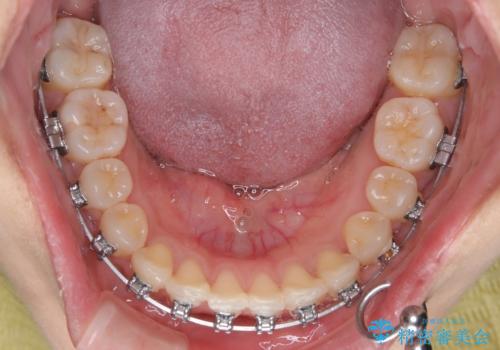

- 矯正装置

- メタルブラケット

- 左上の前歯のがたつきを主訴に来院された患者様です。

上顎歯列が下顎の歯列に対して狭小であり、一部下顎の奥歯が上顎よりも外側に位置している状態でした。

上顎の歯列を拡大しスペースを設け、さらに左上の小臼歯を一本抜歯し左上の八重歯を歯列内に入れ整えていくことにしました。